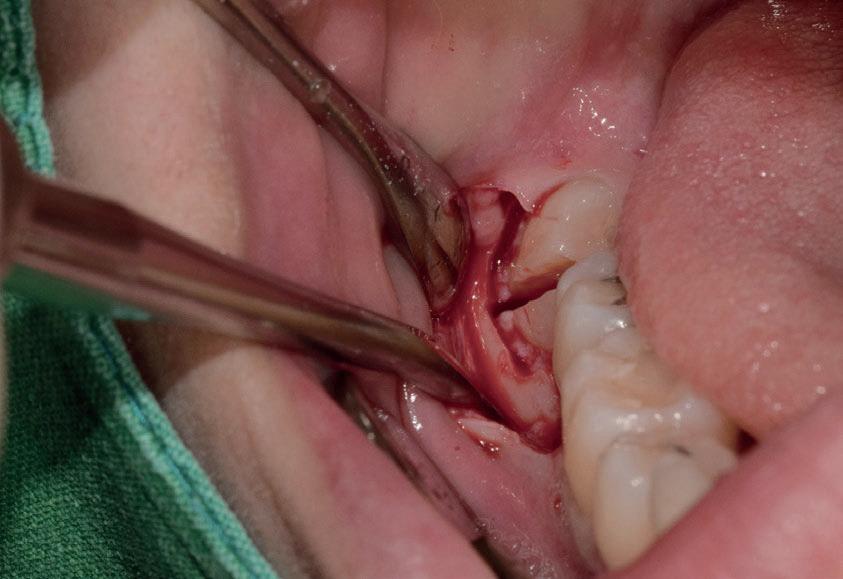

Questo è un paziente di 22 anni ed essendo un amico, ho potuto ben documentare il caso con il suo consenso: il suo dente del giudizio inferiore sinistro è stato estratto utilizzando il manipolo dritto. Figg. 143-149

Figg. 143-149 - Caso 1, paziente di 22 anni: tecnica di estrazione con divisione orizzontale utilizzando il manipolo dritto. Fig. 143 Fig. 144 Fig. 145 Fig. 146 Fig. 147 Fig. 148 Fig. 149